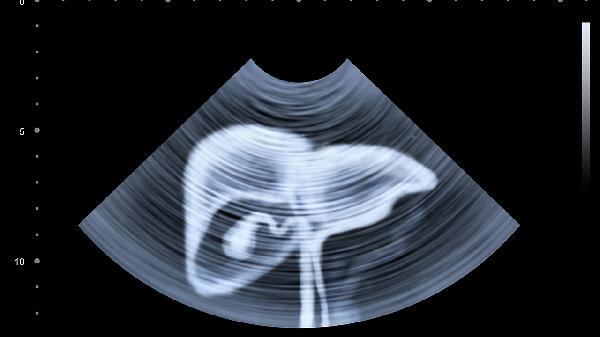

1、腹部超声检查:这是一种无创的影像学检查方法,能够清晰显示腹腔内脏器的结构及异常情况。在检查过程中,患者躺在床上,医生使用一个小型装置在腹部移动,以获取图像。这种检查通常不会带来任何不适,是检查脾脏问题的常用手段。